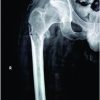

A 63-year-old male presented to emergency with a history of a road traffic accident, in which the patient was riding pillion and was struck by a car moving at high velocity. After emergency stabilization and application of skeletal traction in the trauma bay, he was transferred to the orthopedic unit. The radiographs revealed a “double segmental” fracture of the right femur with no other associated injuries (Fig. 1a-d). The patient was taken up for intramedullary fixation with a cephalomedullary nail the next day. Initially, we tried using Schanz screw to reduce the intermediate fragments and hold them in place, but they interfered with the reaming due to the protruding part in the narrow canal. Subsequently, weber clamps were used on the proximal and intermediate fragments to correct their respective displacements and hold the fracture fragments in reduced positions. The use of a polar screw helped in centering the guidewire in the distal fragment.